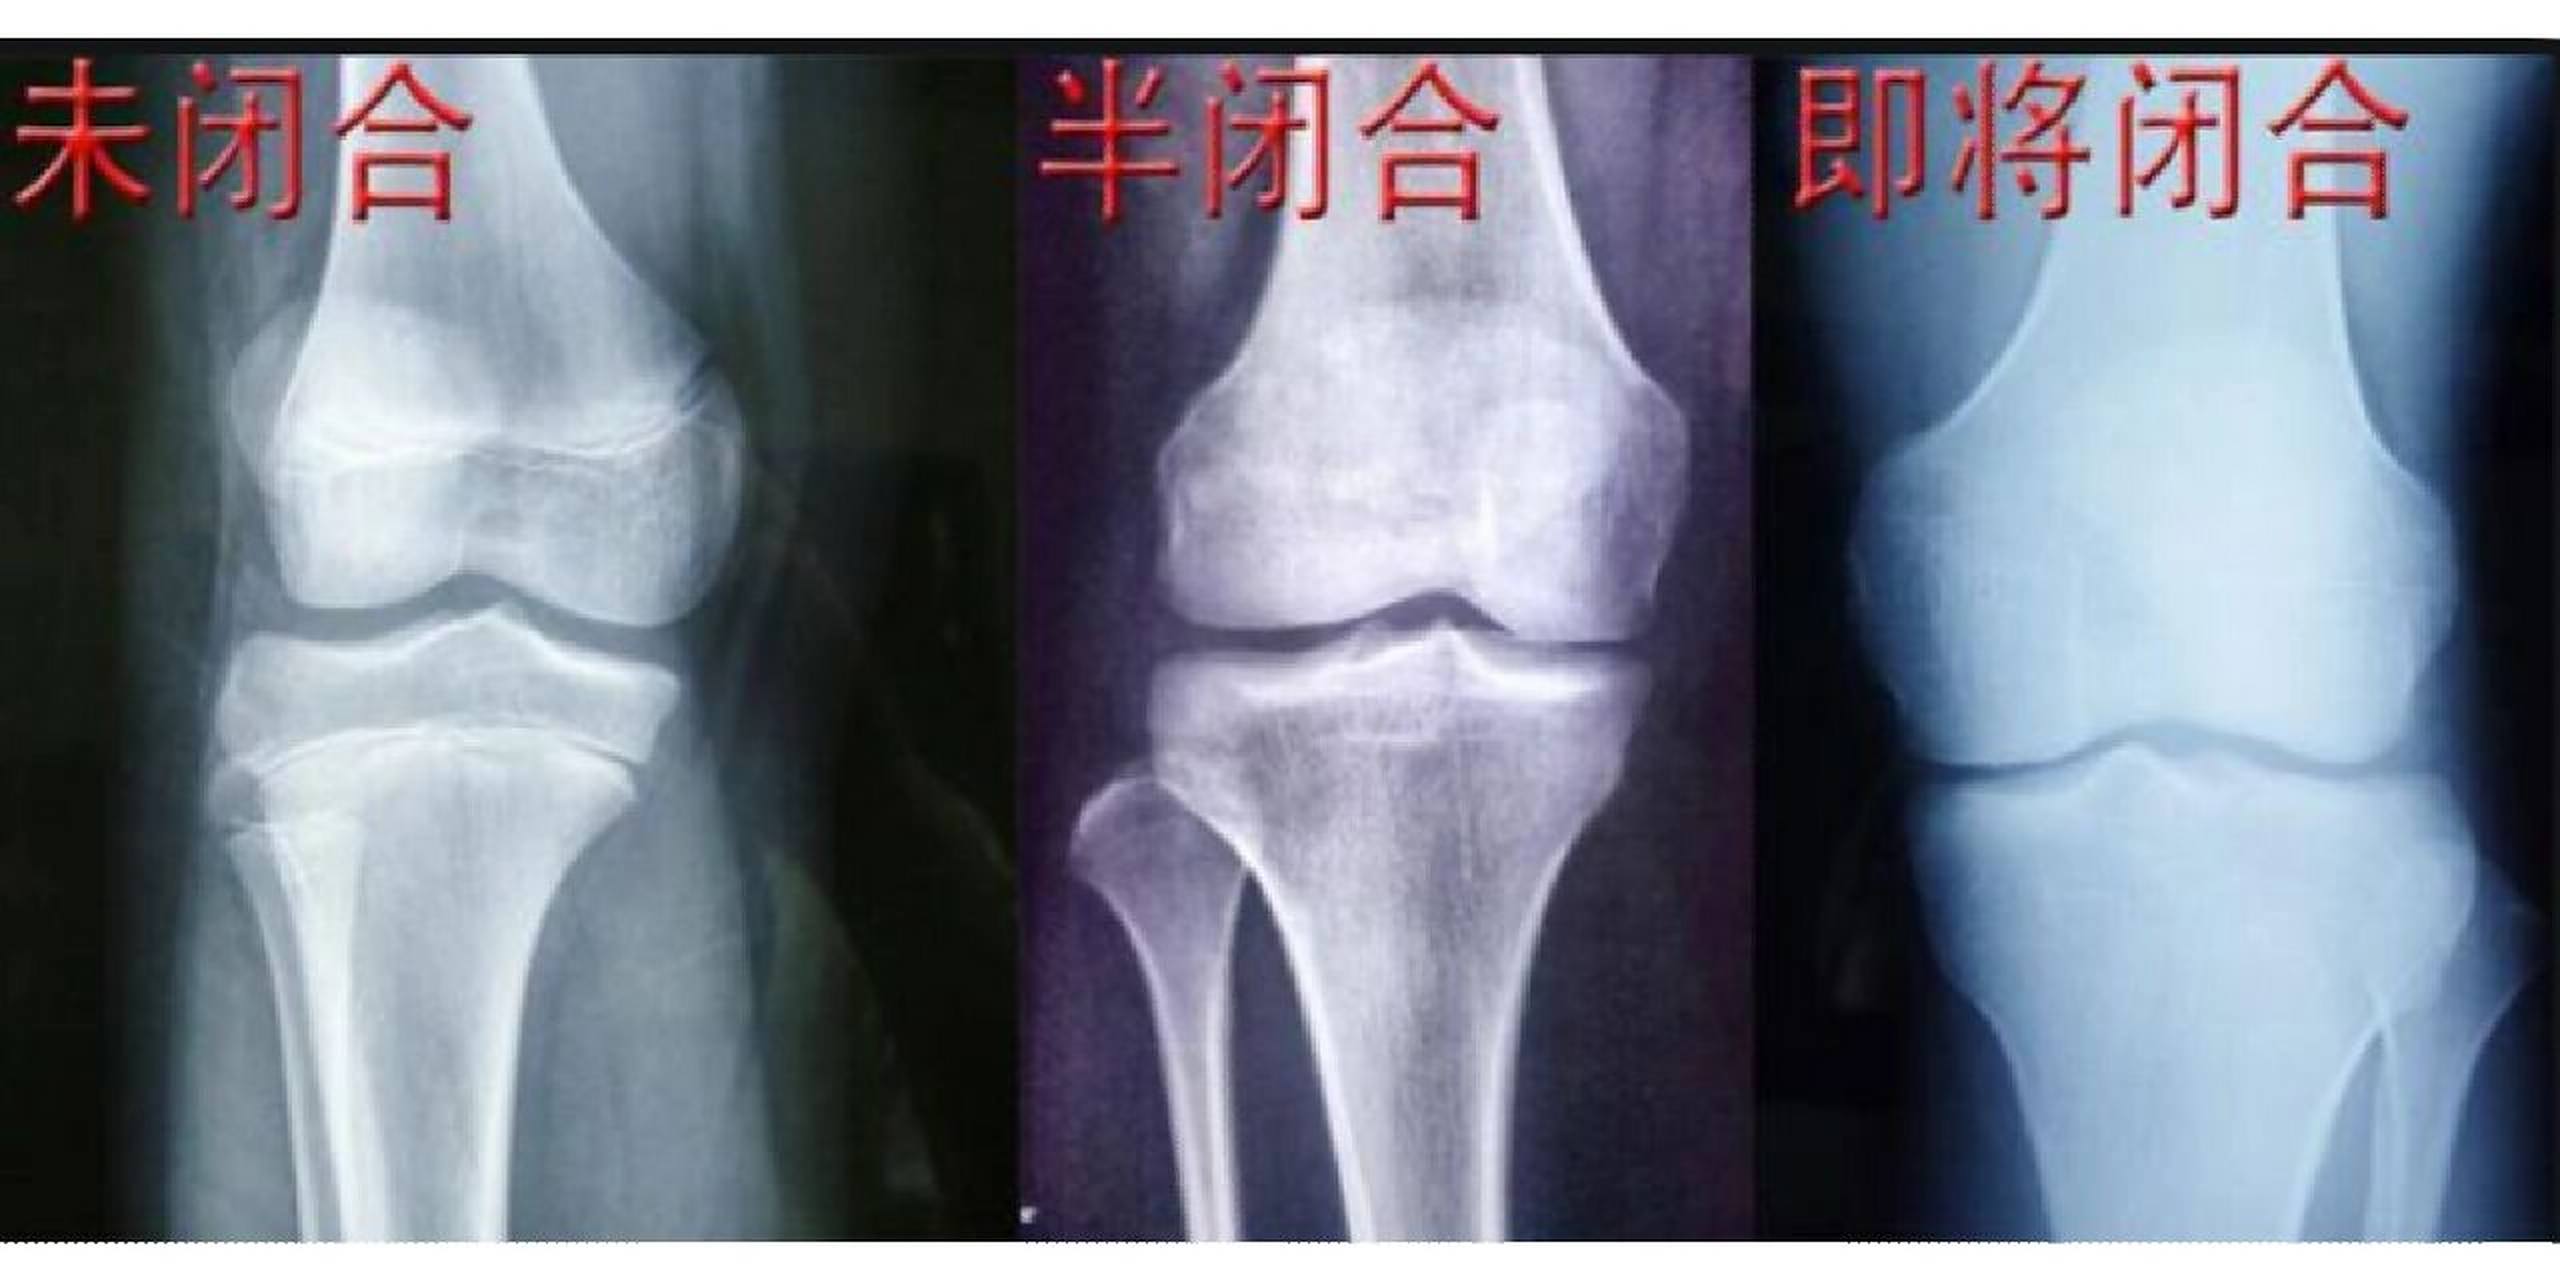

骨骼线闭合检查挂什么科?

1、检查骨骼线可根据不同情况挂以下科室1 骨科骨科是专门诊断和治疗骨骼关节及相关疾病的科室,检查骨骼线属于其常规项目医生可通过X线等影像学检查评估骨骼发育情况,明确骨骼线是否闭合若患者年龄在1218岁之间且存在骨头受...